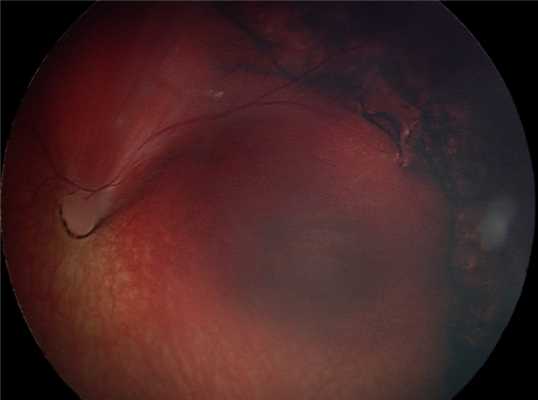

Клинический случай.

Глазное дно ребёнка А. до операции.

Глазное дно ребёнка А. после операции.